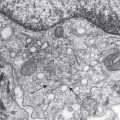

Removal of the epidermis abolishes the perception of itch, suggesting that putative pruritus receptor units are located predominantly within this layer. Light microscopic and ultrastructural studies of human skin have shown the existence of intraepidermal nerve fibers with “free” non-specialized nerve endings extending to the stratum granulosum . A subclass of C fibers in the epidermis that express Mrgprs, in particular MrgprX1, are involved in chloroquine-induced pruritus (see Fig. 5.2F ) . Cathepsin S, an endogenous protease, can cleave and thereby activate both MrgprC11 in mice, which leads to scratching behavior, and MrgprX2 in humans ; this is in addition to its ability to activate PAR-2/4 receptors ( Fig. 5.2 ). In mice, neurons that express MrgprA3 relay itch-specific information to the spinal cord .

Histamine is the archetypal mediator of signs and symptoms of inflammation, including pruritus. In the skin, histamine is contained primarily within the granules of dermal mast cells. Histamine can be released from mast cells upon activation of a range of receptors, including the high-affinity IgE receptor (FcεRI), the KIT receptor for stem cell factor, and receptors for neuropeptides (e.g. substance P, NGF) and complement C5a. In IgE-mediated acute urticaria, histamine is released when a specific antigen/allergen cross-links adjacent receptor-bound specific IgE antibodies. In autoimmune chronic urticaria, similar cross-linking occurs via functional circulating IgG that react with epitopes expressed on the α-chain of adjacent FcεRIs or less commonly anti-IgE autoantibodies (see Fig. 18.3 ). Histologically, dermal mast cells and unmyelinated neurons are closely juxtaposed (see Fig. 5.2B, C, E ), raising the possibility of a close (“synapsis-like”) functional relationship between the immune and nervous systems.

Human dermal mast cells produce two proteases, tryptase and chymase . Tryptase released by activated mast cells cleaves PAR-2, a G protein-coupled receptor present on C-fiber terminals (see Fig. 5.2B, D ); this exposes a tethered ligand domain and thereby “self-activates” PAR-2, leading to itch transmission. PAR-2 activation results in local release of neuropeptides, including substance P and calcitonin gene-related peptide, which induce neurogenic inflammation . Kallikrein and cathepsins in the skin can also activate PAR-2 in a similar manner. In addition, cleavage of murine MrgprC11 or human MrgprX2 by cathepsin S activates these receptors and evokes itch (see above).